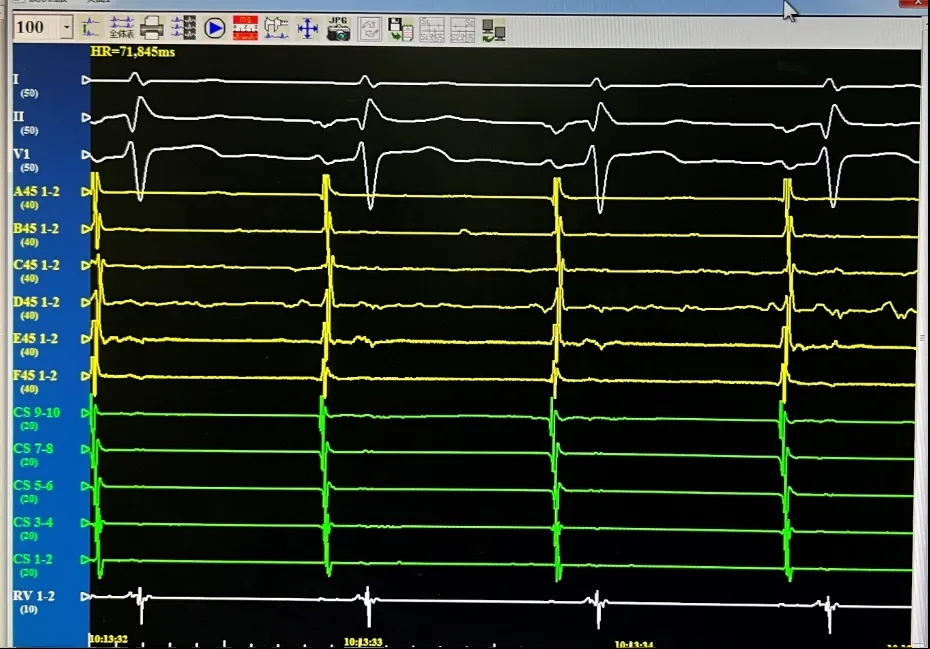

消融导管呈网篮与花瓣形态下放电。

LSPV,消融前后电位。消融后电位即刻消失。